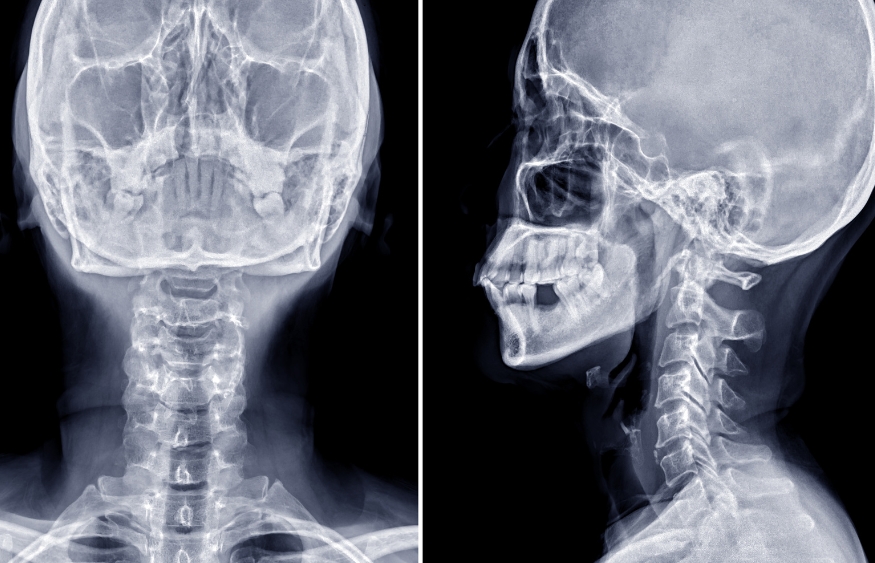

A non-contrast CT scan revealed something never before published in any spine classification manual:

- The C5 vertebral body had suffered a retropulsion fracture, meaning it had collapsed and pushed backward into the spinal canal.

- A secondary fracture was visible in the upper back portion of the C6 vertebra.

- Yet remarkably, there was no damage to the facet joints or pedicles, which are usually compromised in injuries this severe.

This created a “nutcracker-like” effect—a brutal compression between vertebrae, where the C5 was literally crushed and forced backward into the spinal canal. The result: direct compression of the spinal cord, which explained the young man’s rapid deterioration.